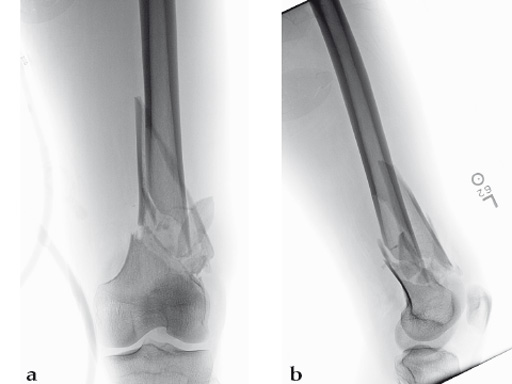

Case 1: A 30-year-old man was involved in a motor vehicle collision and sustained an isolated extraarticular multifragmentary supracondylar femoral fracture (33-A3).